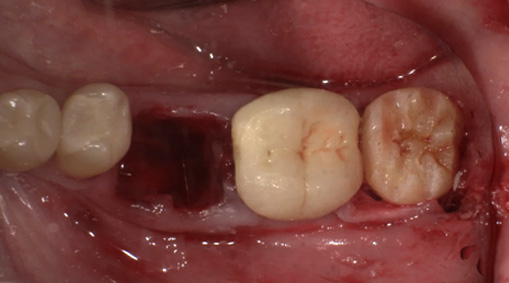

親しらずを抜歯して、移植します。

歯の固定や傷口を縫合します。